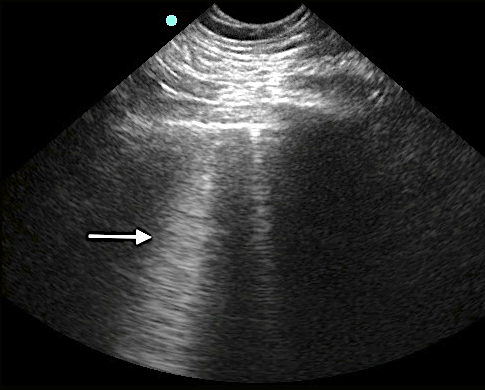

- Mirror image artifact60

- Sound waves reflect off the highly reflective diaphragm, encounter liver tissue, are reflected back to the diaphragm, and then return to the transducer. Based on the time taken for the sound waves to return to the transducer, the machine incorrectly assumes that the initial beam traveled along a linear path and reached the liver tissue deep to the diaphragm. The liver is thus mapped falsely in the deeper location.

- Figure 15. Mirror image artifact